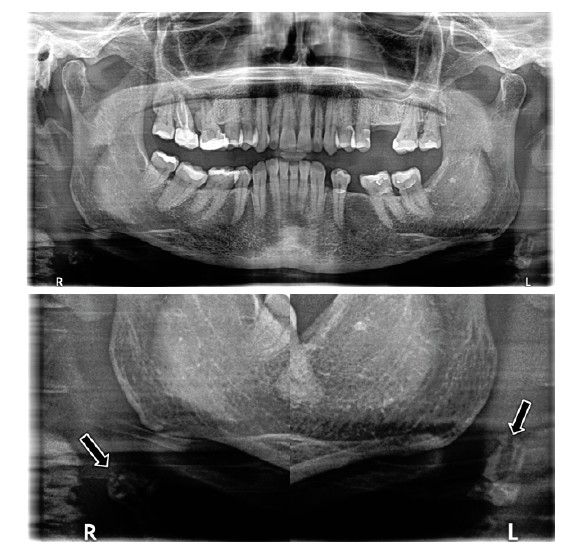

Estas calcificaciones que, generalmente se localizan en la bifurcación carotídea, se presentan como masas radiopacas en la región de la radiografía panorámica correspondiente a los tejidos blandos del cuello, en una zona aproximada entre las vértebras cervicales C2, C3 y C4, a una distancia aproximada entre 1 y 4 cm posteroinferior al ángulo mandibular13. Pueden variar en tamaño y forma, siendo lineales verticales, nodulares o heterogéneas, y pueden presentarse de manera unilateral o bilateral, así como ser únicas o múltiples13-15.

El objetivo de esta publicación es contribuir a la prevención de los problemas cerebrovasculares desde la clínica dental, mediante la presentación de tres casos clínicos en los que se detectaron de manera casual calcificaciones carotídeas durante un examen radiográfico de control, realizado mediante una radiografía panorámica, en pacientes con patologías periodontales en fase de mantenimiento.